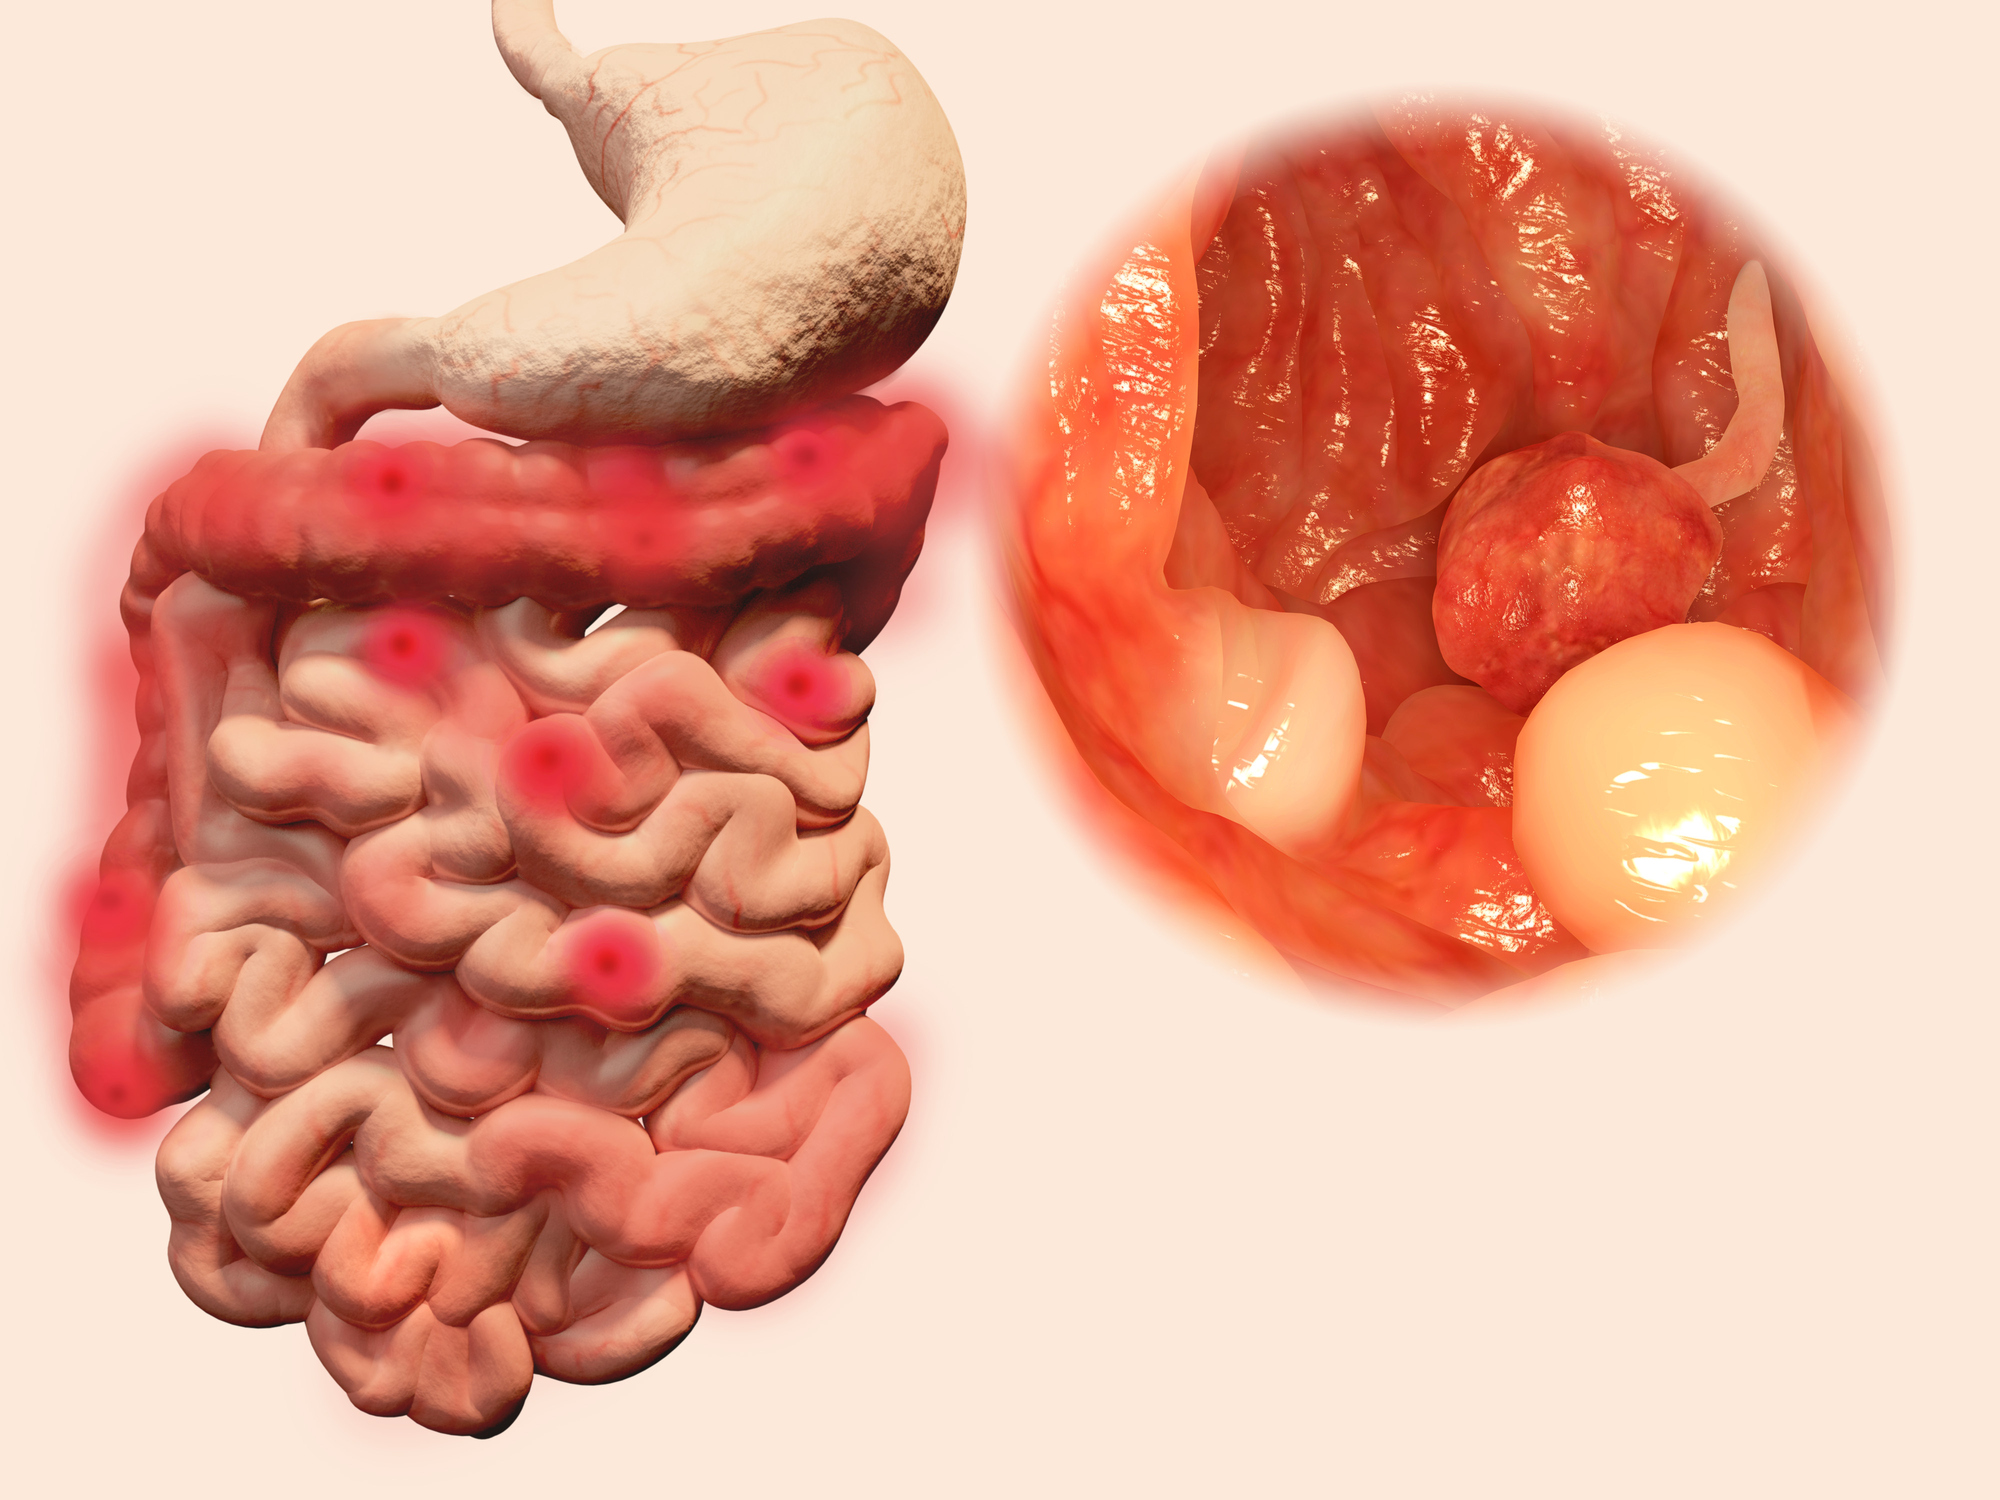

This week’s health news roundup includes recent stories about celiac disease, ulcerative colitis, rheumatoid arthritis, fibromyalgia, and inflammatory bowel disease (IBD). This week, we discussed the benefits of going gluten-free in celiac disease, possible treatment for ulcerative colitis, risk of cancer in rheumatoid arthritis, positive impact of aquatic aerobics on fibromyalgia patients, and the problem ...click here to read more